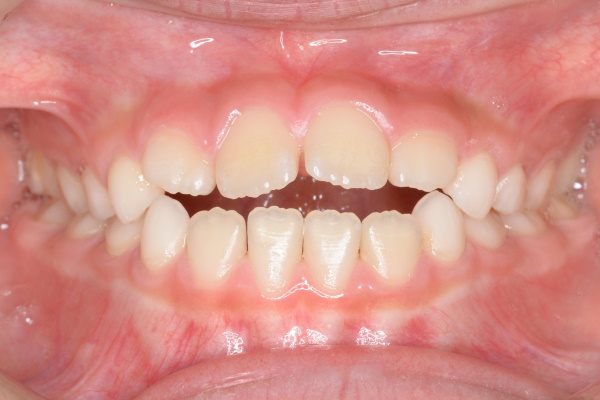

| 年齢・性別 | 7歳女児 |

| 治療期間 | 1年3か月 |

| 抜歯 | なし |

| 治療費 | 37万円(調整費、保定費まで含む総額制) |

| 備考 | インビザラインファースト |

| リスク・副作用 | 痛み・治療後の後戻り・歯根吸収・歯髄壊死・歯肉退縮 |